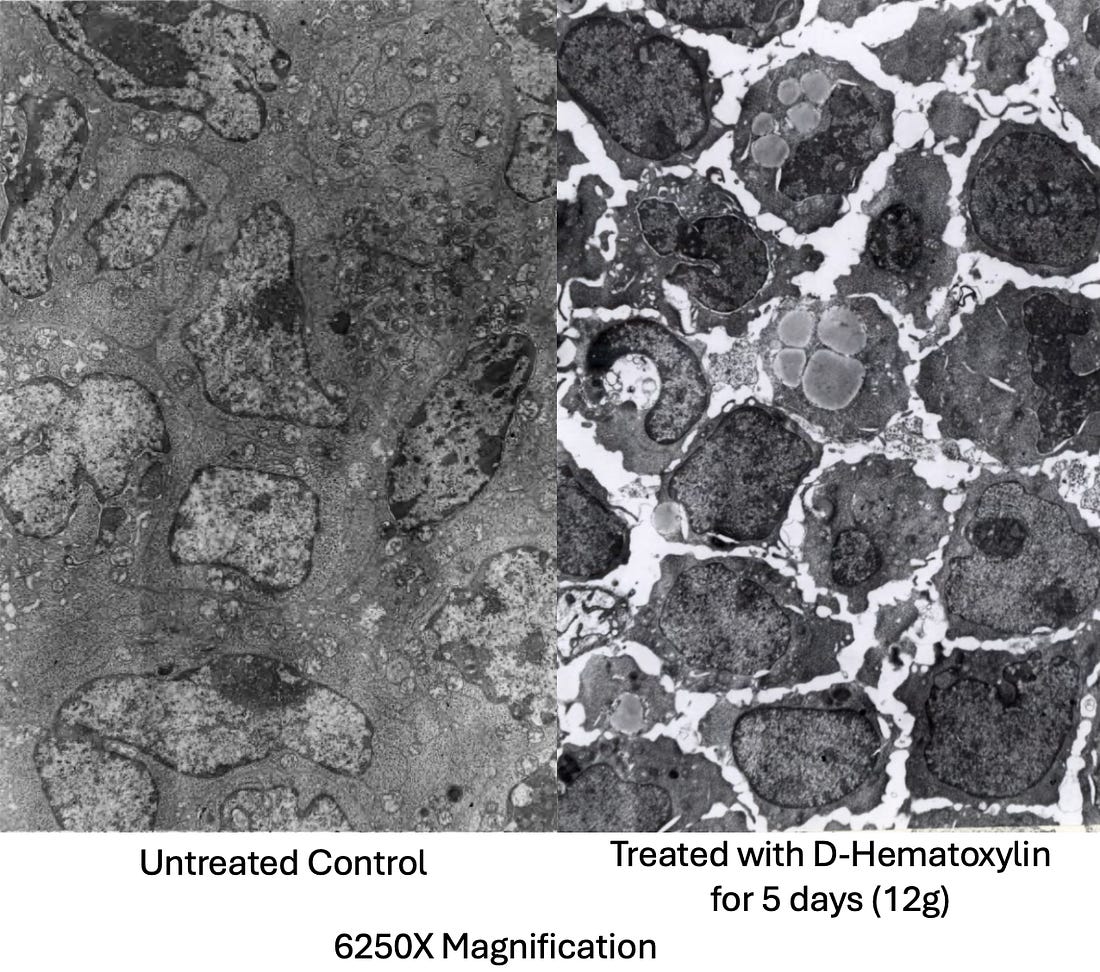

To do so, Rogers implanted mice with rapidly growing lymphosarcoma cells (which typically resulted in death 11 days), then sacrificed and dissected them shortly before their expected time of death and visually examined everything (including under both a light and electron microscope). The mice in turn received either nothing, DMSO alone, hematoxylin alone (which was dissolved in saline through heating and agitation), or varying doses of D-hematoxylin (0.2mL of 90% DMSO mixed with either 2, 5, 8 or 12mg of hematoxylin in DMSO). DMSO and hematoxylin alone were observed to have no side effects, but also do not affect the growing cancers, while D-hematoxylin inhibited the cancers in a dose dependent fashion (and did so without side effects or affecting non-cancerous tissue). Note: since IVs (which are typically the most potent way to administer DMSO or D-hematoxylin) are challenging to give to mice, Rogers instead administered the treatments through intraperitoneal or subcutaneous injections and oral feeding (and likewise Tapia in his LD50 study only did intraperitoneal injections). There, Rogers discovered that subcutaneous and intraperitoneal D-hematoxylin gave similar notable results, while oral D-hematoxylin produced similar but less extensive results (which dovetails with Tucker’s observation he could also obtain clinical results with oral D-hematoxylin). With intraperitoneal D-hematoxylin, the lowest 2mg dose caused slight alterations of the tumor cell morphology, 5mg caused the same changed but in a larger area, 8mg sometimes shrank the tumor, while 12mg caused a complete destruction of the tumor and shrank the tumor by approximately 33% (which extended the mice’s lifespan by approximately 27%). Additionally, while the mice were typically sacrificed four days after completing five D-Hematoxylin treatment, in one case they were instead sacrificed a day after, and there, early stages of degeneration were observed, demonstrating D-hematoxylin initiates a therapeutic process that continues long after the treatment has been discontinued. Additionally, at all doses, D-hematoxylin was found to affect the tumor’s center first, then spread outward, sparing the periphery from the effects observed throughout the rest of the tumor. However, at higher doses (8 or 12 mg), minor changes were also detected in the peripheral regions. This pattern is highly unusual, as chemotherapy agents typically target the cancer from the periphery inward (along with a smaller number that destroy the cancer in a more scattered and heterogeneous manner). This in turn suggests D-hematoxylin is able to penetrate the barriers which normally allow cancer cells to resist chemotherapies (which as I showed previously DMSO has been demonstrated to do for other chemotherapies). Similarly, when individual cells were observed, the damage initially began in the nucleus (with the appearance of nucleolar lesions and loss of peripheral chromatin nuclei), suggesting D-hematoxylin had an affinity for DNA (which hematein does). Following this, the cancer cells, in successive stages, began to break down and digest themselves (autolysis), a death process different from the apoptosis typically observed when DMSO alone eliminates cancers (that was potentially due to DMSO releasing digestive enzymes from lysosomes). Finally, as this progressed, debris from other tumors increased and white blood cells began to invade the tumors to eliminate them. Note: in the mice, if cancer debris increased too quickly, it could cause kidney failure (as there was too much for the kidneys to process. Subsequently, Morton Walker analyzed that dissertation and concluded that D-hematoxylin was dissolving the extracellular matrix (which can also been seen in many other pictures within the study) and that this matrix dissolving deprived the cancer cells of necessary nutrients, causing them to starve (which likewise could explain the gradual degenerative process D-hematoxylin initiates in cancer cells starting from the center rather than the periphery). Note: other processes could also explain these changes (e.g., anoikis, a form of cell death triggered by detaching from the extracellular matrix rather than starvation, could trigger cell death beginning in the center of the tumor, or alternatively, the loss of the ECM could be an effect of cell death rather than a cause and not play a contributing role to the changes observed). Sadly, other than Rogers’ dissertation (which just scratches the surface of what was happening), no one has conducted the cellular experiments to determine why D-hematoxylin works. Fortunately, a team in Ecuador (where research is fairly affordable) is presently trying to get the funding to do that research, so if anyone could help support funding that research, please let us know (e.g., in the comments below). Note: the only other study I have been able to locate that assessed the effects of DMSO combined with hematoxylin was a study that found DMSO effectively washed hematoxylin away from starch granules in pollen cells but not from the nucleus, again implying D-hematoxylin has a special affinity for the nucleus of cells. This study, in turn, was conducted because hematoxylin would consistently darkly stain starch granules, making it impossible to see out the pollen cell’s nucleus. Protein Kinase CK2Protein Kinase CK2 , when dysregulated, has been implicated in hundreds of diseases (e.g., viral infections including COVID-19, autoimmune diseases, and neurological conditions). Of those, its best known for playing a key role in cancer (e.g. its activity is often elevated in various cancers, which contributes to tumor progression and poor prognosis). Some of its carcinogenic effects include: •CK2 phosphorylates hundreds of proteins which allows it to both activate key cancer signaling pathways such as PI3K/Akt, mTORC1, and β-catenin1,2 (which promotes cancer cell proliferation, survival, angiogenesis, invasion, and metastasis).and to inhibit key tumor suppressors like PTEN and p53. •CK2 modulates the Warburg effect, hence triggering a metabolic switch where cancer cells stop relying on oxygen for energy production (something many over the years believed is a root cause of cancer). Additionally, CK2 also preserves mitochondrial function to support the high energy demands of growing tumor. •Cancer CK2 activity suppresses the immune system’s ability to eliminate cancer cells, while numerous studies show that inhibiting CK2 activity enhances the immune system’s ability to eliminate cancers. •CK2 makes cancer cells resistant to programmed cell death and hence makes them continue to proliferate. Additionally, CK2 makes cancer cells resistant to anoikis